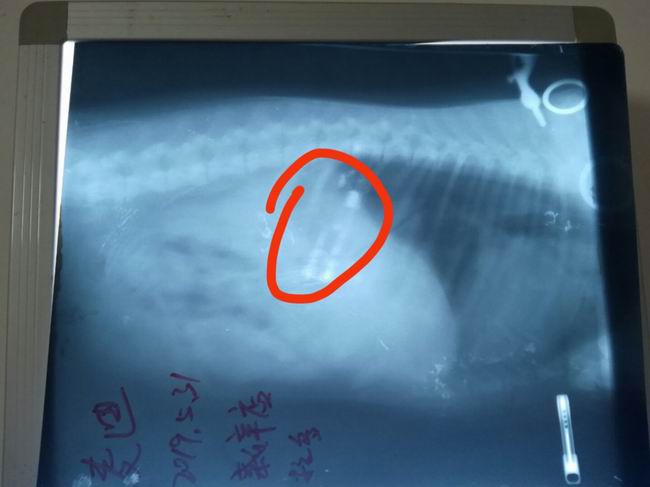

拉布拉多麥迪誤吞入打火機,主人來我院進行治療,經(jīng)過x光檢查,異物(打火機)在胃內(nèi)清洗可見,初步通過藥物促使異物排出,若不能自主排出需要進行手術(shù)取出異物。

溫馨提示:一定要看好自己的愛寵,防治異食發(fā)生!!!